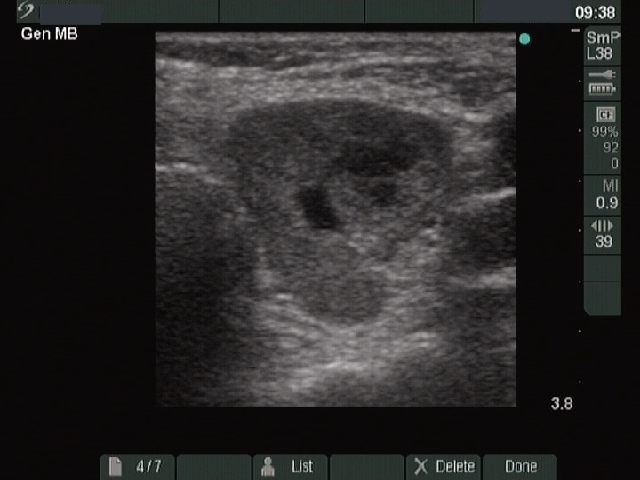

Benign nodular hyperplasia - Case 41. (ultrasonographic picture 4)

Right lobe, longitudinal scan